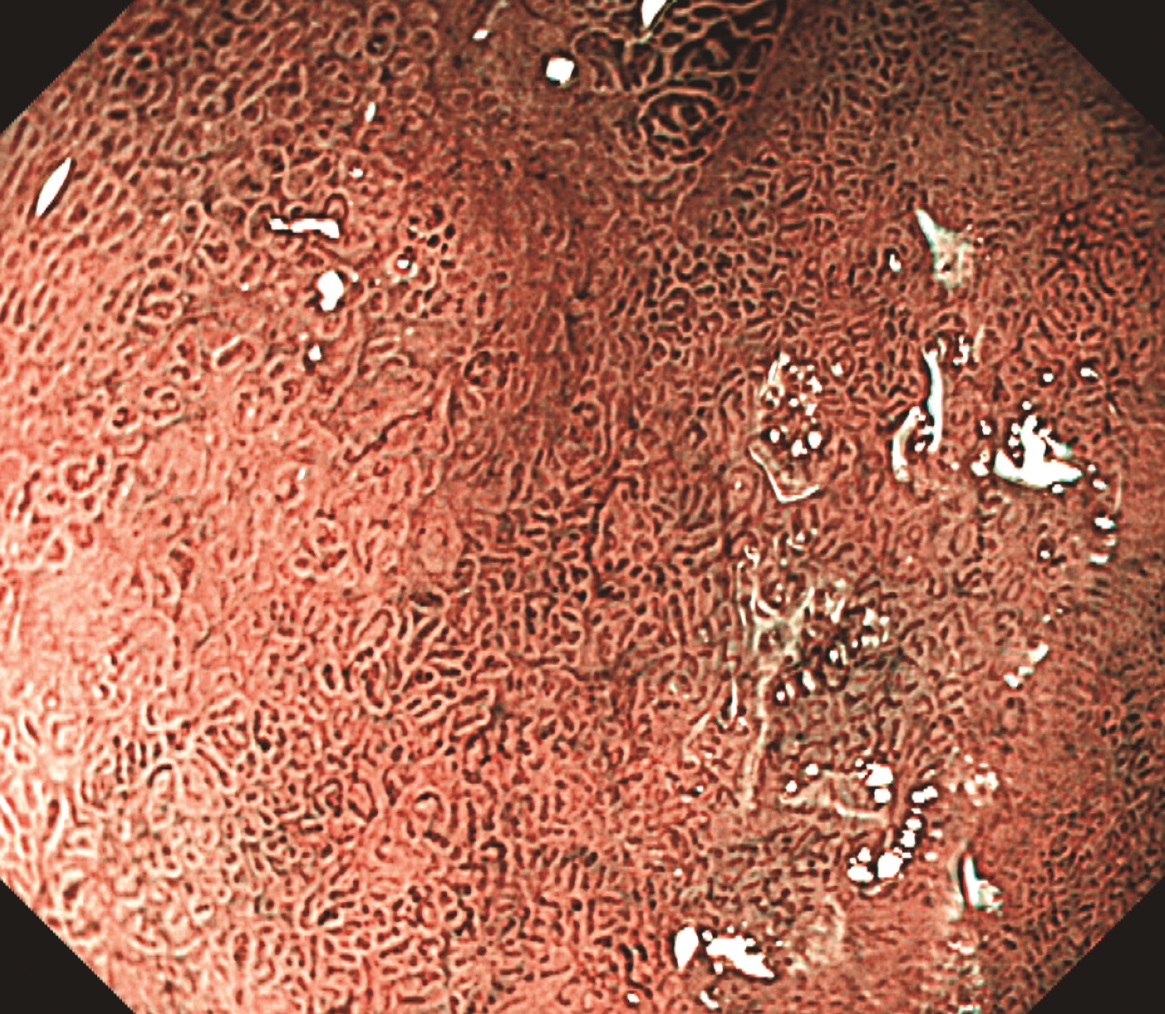

通常内視鏡像

背景はまだらな発赤を認め,萎縮粘膜と診断する.

前庭部小彎に発赤粘膜を認め,その周囲には黄色〜軽度発赤調の領域が広がっているのを認める.しかし,色調や段差で境界は不明瞭と思われた.

NBI弱拡大像

NBI弱拡大では,背景は整った絨毛様構造であり,一部light blue crest(LBC)陽性を認め,腸上皮化生粘膜と診断する.

一方,病変内部では大小不同を伴う小型で密な絨毛様構造を認め,white zone(WZ)の幅は不均一である.

背景粘膜と病変内部の構造差から,境界を黄点線と考えた(図3).